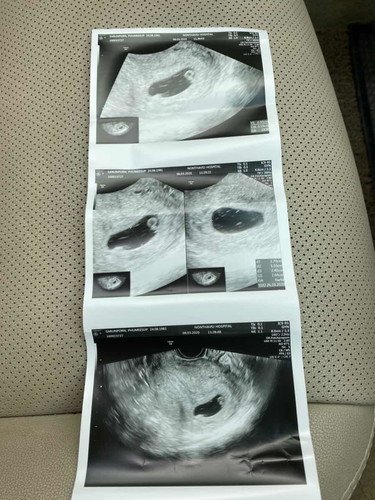

6 week ตรวจผ่านช่องคลอด เจอถุง เจอไข่แดง แต่ยังไม่เจอตัวน้อง. เครียดกลัวท้องลม เพราะอายุ 38 แล้ว